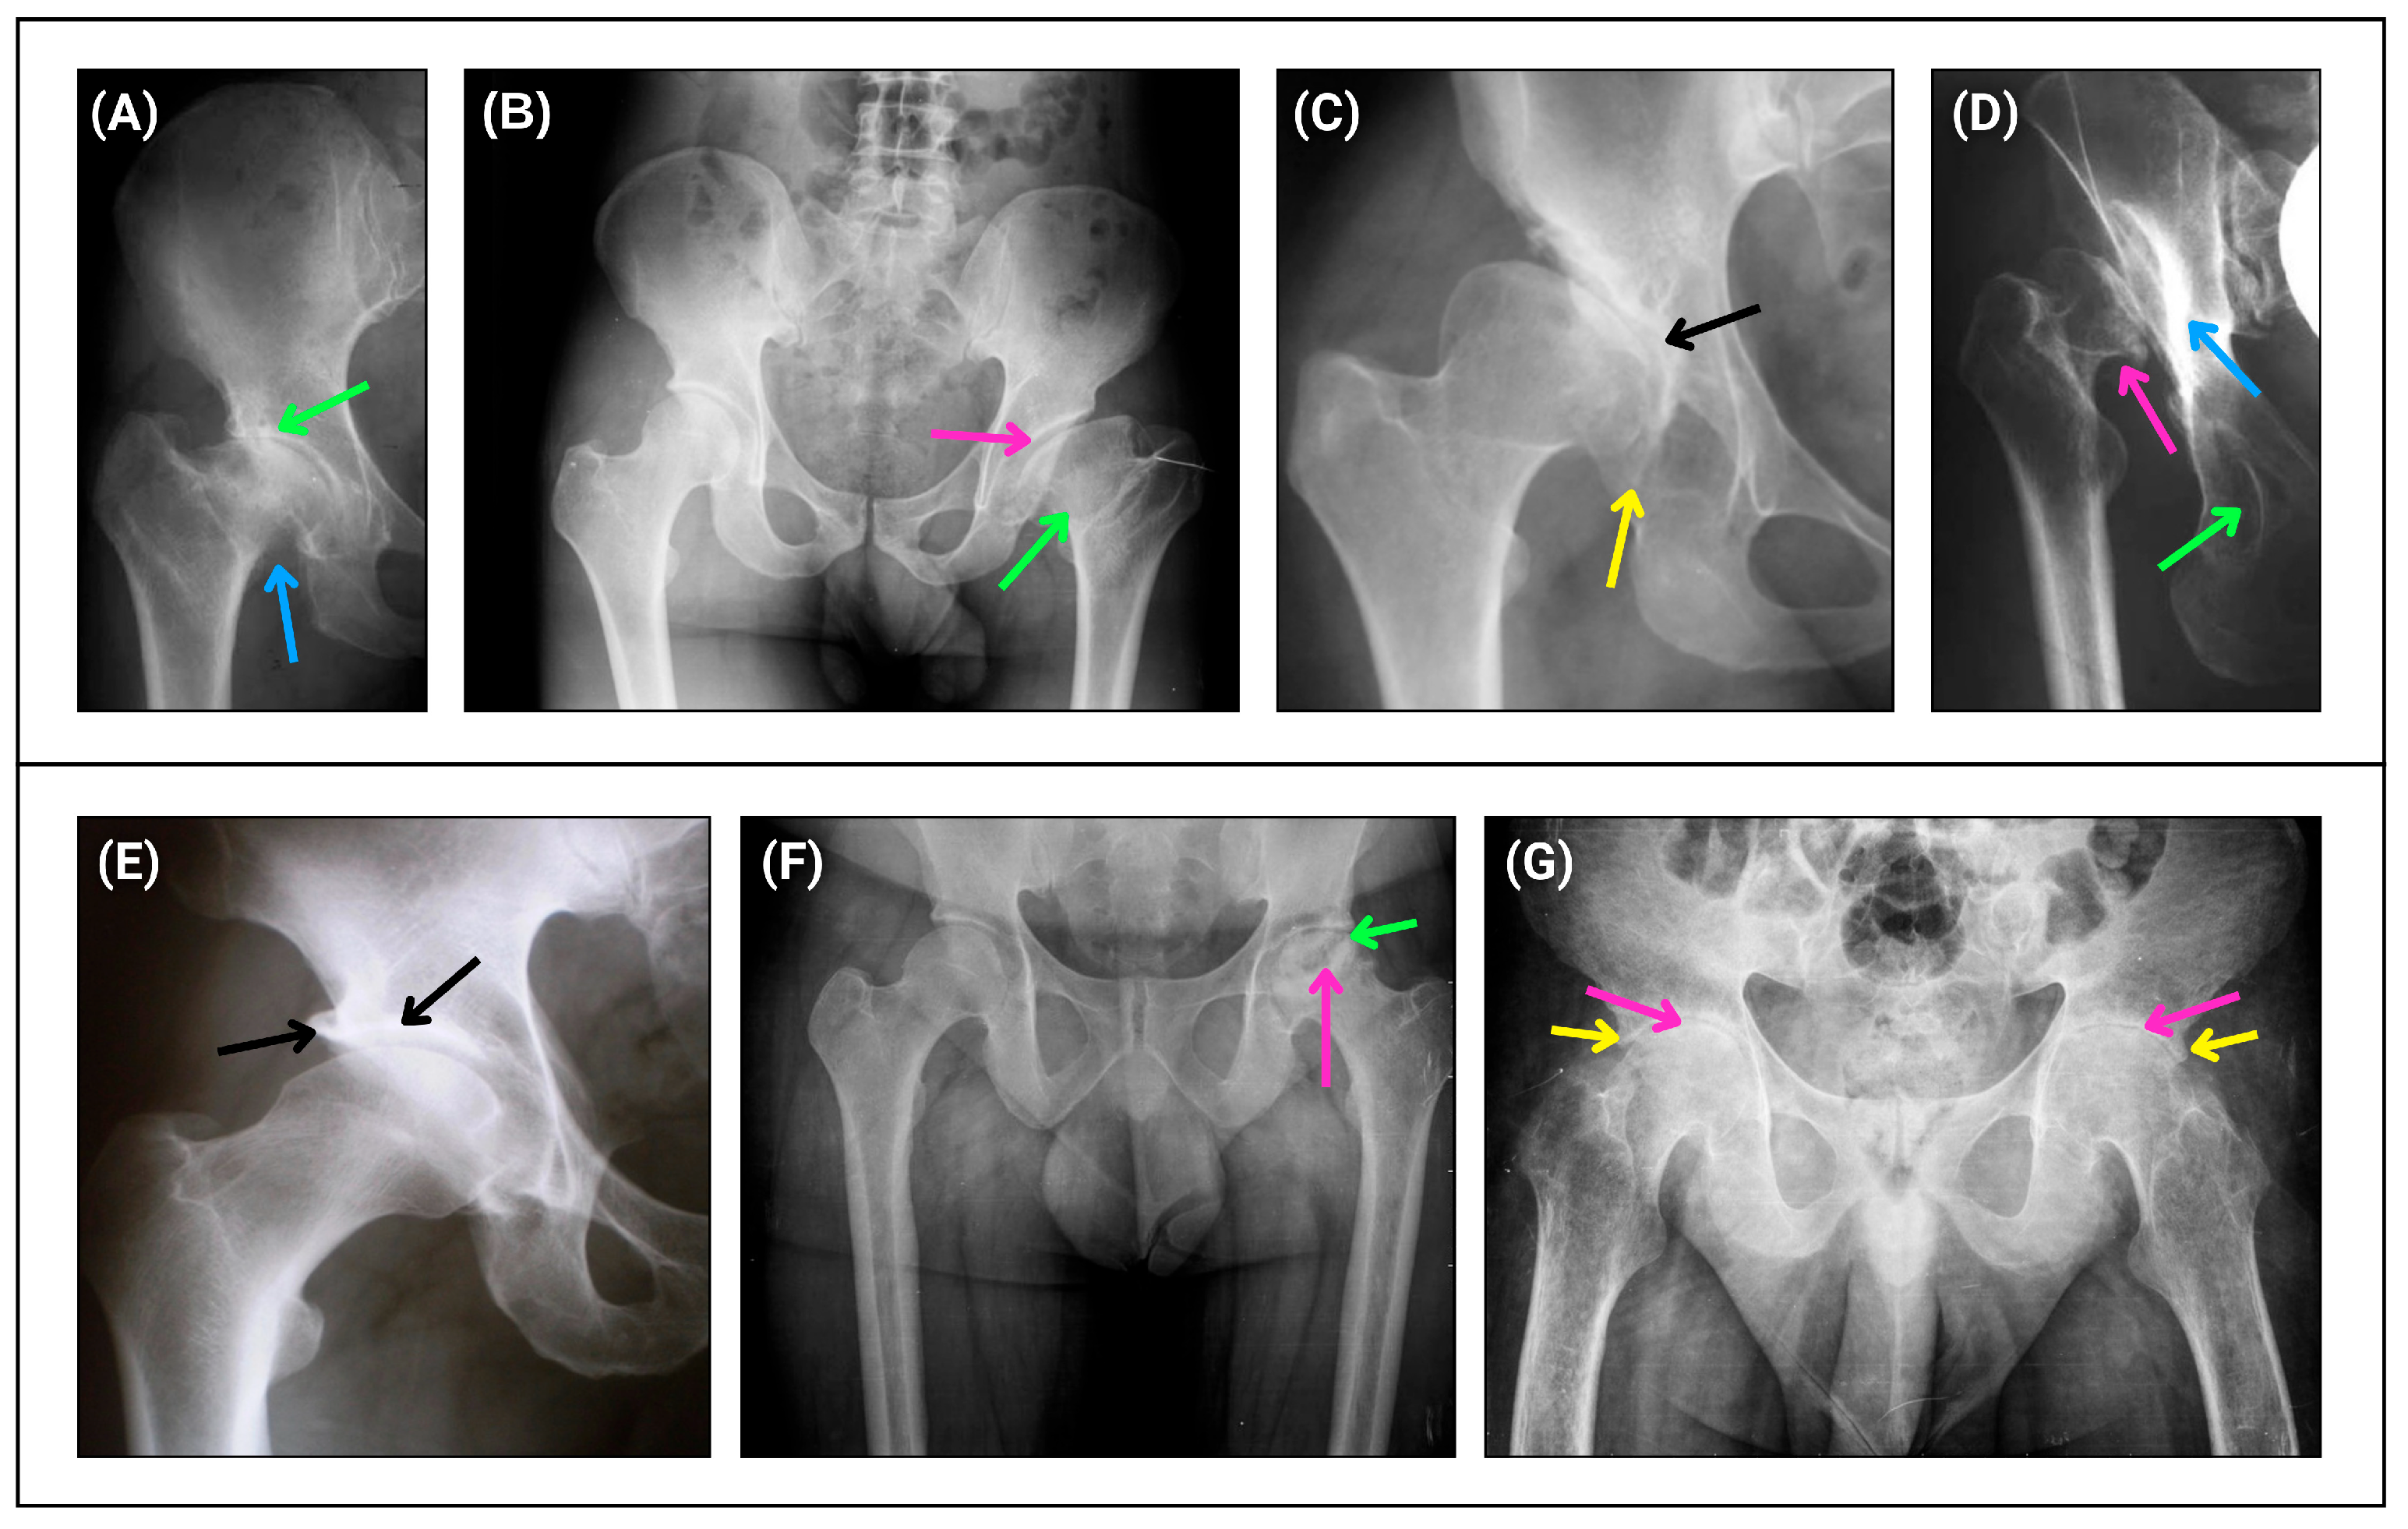

DDH was diagnosed radiographically by the presence of one of the following parameters: center–edge angle less than 20º and break in Shenton’s arc. The disease was graded from 1 to 4 according to Crowe’s classification based on the severity of the dysplasia. Grade 1 is characterized by a reduced hip (incongruent but without subluxation) (Figure 4A); grade 2 by less than 50% hip dislocation (low dislocation) (Figure 4B); grade 3 by 50 to 100% hip dislocation (low dislocation) (Figure 4C); and grade 4 by more than 100% hip dislocation (high dislocation) (Figure 4D). The Hartofilakidis classification was also used, categorizing cases as reduced hip (without subluxation), low dislocation, and high dislocation. DDH cases with secondary coxarthrosis (hip osteoarthritis) were also graded according to the Tonnis classification, which includes four progressive grades, including Tonnis angle greater than 10° and Sharp angle greater than 45°. Coxarthrosis was diagnosed by plain pelvic radiography, which showed a reduction in the hip joint space, with a normal value of 3mm. Thus, according to the Tonnis classification, in grade 0, there is no disease; therefore, the joint is normal. Grade 1 represents a mild reduction in the joint space between the acetabulum and the femoral head (Figure 4E). Grade 2 shows a moderate joint space reduction with osteophytes, metaphyseal cysts, and sclerosis (Figure 4F). Grade 3 exhibits a marked reduction in the joint space, with more prominent osteophytes, an increased presence of subchondral cysts, and increased bone sclerosis (Figure 4G).

Figure 4. Radiographic representations of the Crowe (AD) and Tonnis (EG) hip classifications of dysplasia cases. (A) The green arrow indicates a reduced joint space with a reduced femoral head in the acetabulum, and the blue arrow indicates a short femoral neck (Crowe 1 and no subluxation). (B) The pink arrow indicates a femoral head with loss of acetabular coverage and the green arrow indicates a short femoral neck (Crowe 2 and low dislocation). (C) The black arrow indicates a previous acetabular roof with advanced degenerative changes due to abnormal contact between the femoral head and the acetabulum, and the yellow arrow indicates a previous acetabular roof (Crowe 3 and low dislocation). (D) The blue arrow indicates a new acetabulum due to abnormal contact between the parts, the green arrow indicates the previous/native acetabulum, and the pink arrow indicates a dislocated and deformed femoral head (Crowe 4 and high dislocation). (E) The black arrow on the left indicates an osteophyte and the black arrow on the right indicates a sclerosis of the acetabular roof (Tonnis 1). (F) The pink arrow indicates a cyst in the femoral head, and the green arrow shows a moderate reduction in the joint space (Tonnis 2). (G) The pink arrow indicates advanced joint space reduction and the yellow arrow indicates an osteophyte in the acetabular roof (Tonnis 3).